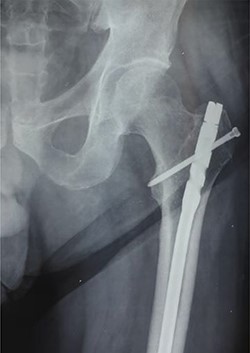

Anteroposterior radiograph showing a buried intramedullary nail.